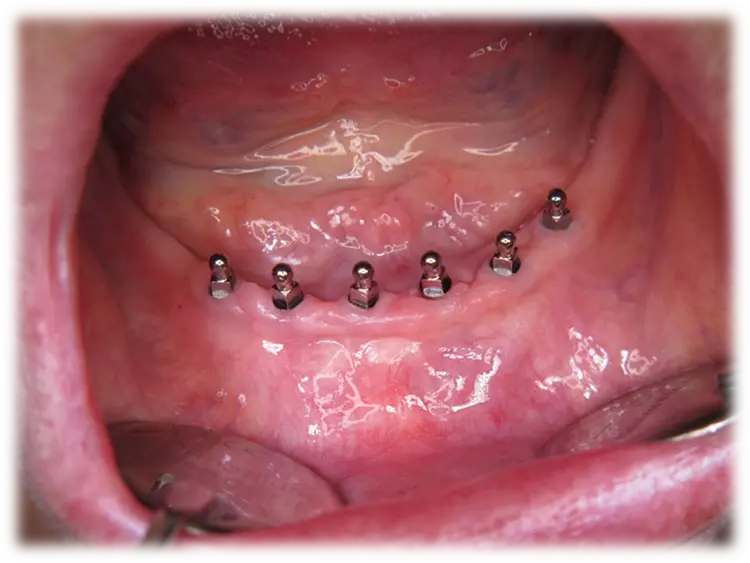

Die klinische Untersuchung ergab folgendes:

BOP | N = 49 (16,1 %), |

| Pusaustritt | N = 4 (1,3 %) |

| Keine Lockerung | N = 304 (99,7 %) |

| ST ≤ 3 mm | mesial und bukkal an distal und oral an |

| ST von 5 oder 6 mm | N = 1 (0,3%) |

| MW (StA) mesialer periimplantärer Knochenabbau | 0,60 ± 0,79 mm |

| MW (StA) distaler periimplantärer Knochenabbau | 0,58 ± 0,78 mm |

Die Messung vom Implantatstabilitätsquotient ISQ am Tag der Nachuntersuchung ergab eine Spanne von 14 – 86 mit einem Mittelwert von 71,45 +/- 8,1 (Abb. 6 und 7). Es wurde zusätzlich eine ISQ-Analyse nach Implantattyp vorgenommen.